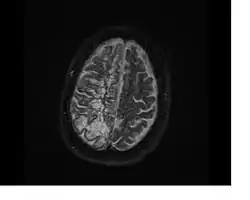

In humans, perivascular spaces surround arteries and veins can usually be seen as areas of dilatation on MRI images. While many normal brains will show a few dilated spaces, an increase in these spaces may correlate with the incidence of several neurodegenerative diseases, making the spaces a topic of research.[4]

Perivascular spaces are most commonly located in the basal ganglia and white matter of the cerebrum, and along the optic tract.[13] The ideal method used to visualize perivascular spaces is T2-weighted MRI. The MR images of other neurological disorders can be similar to those of the dilated spaces. These disorders are:[7]

Perivascular spaces are distinguished on an MRI by several key features. The spaces appear as distinct round or oval entities with a signal intensity visually equivalent to that of cerebrospinal fluid in the subarachnoid space.[7][14][15] In addition, a perivascular space has no mass effect and is located along the blood vessel around which it forms.[14]

The clinical significance of perivascular spaces comes primarily from their tendency to dilate. The importance of dilation is hypothesized to be based on changes in shape rather than size.[13] Enlarged spaces have been observed most commonly in the basal ganglia, specifically on the lenticulostriate arteries. They have also been observed along the paramedial mesencephalothalamic artery and the substantia nigra in the mesencephalon, the brain region below the insula, the dentate nucleus in the cerebellum, and the corpus callosum, as well as the brain region directly above it, the cingulate gyrus.[5] Upon the clinical application of MRI, it was shown in several studies that perivascular space dilation and lacunar strokes are the most commonly observed histological correlates of signaling abnormalities.[13]